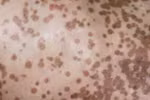

Nguyên nhân dẫn đến căn “bệnh lạ” khiến ông Điền bị lột da, toàn thân đen sịt và giảm hơn 1/2 trọng lượng cơ thể là do ký sinh trùng từ chó, mèo gây ra.